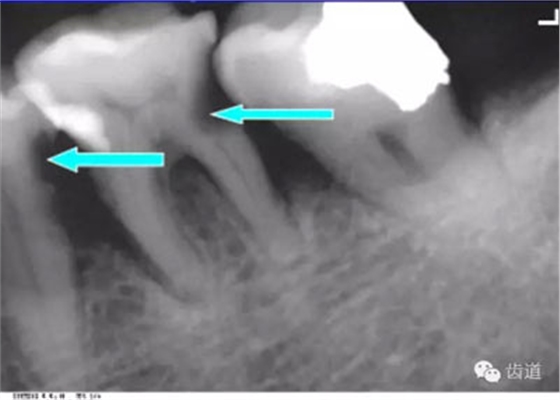

牙頸部Burnout征象:有時(shí)因投照技術(shù)問(wèn)題而造成牙頸部近中或遠(yuǎn)中呈低密度影像,位于牙釉質(zhì)和牙槽嵴頂之間。